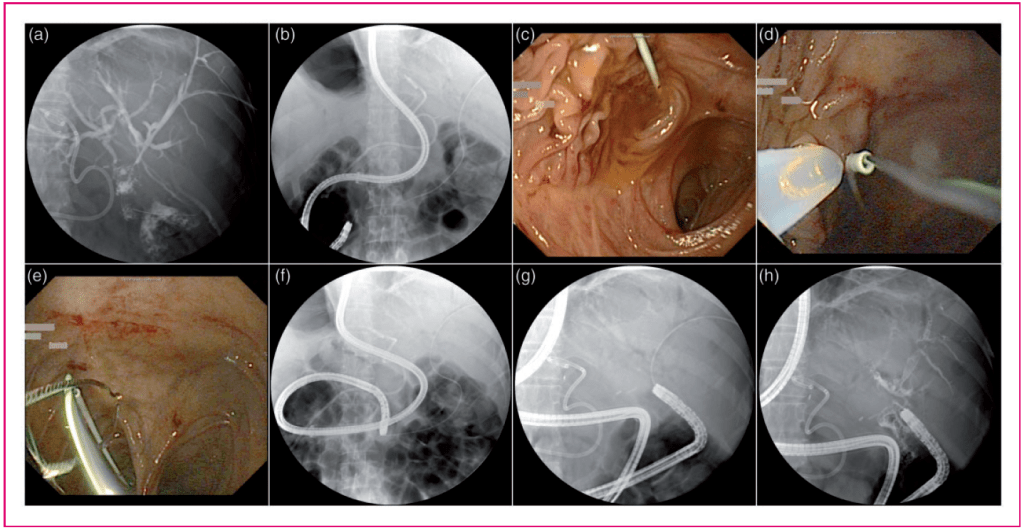

Figure 1. Imaging of a performed percutaneous-transhepatic-endoscopic rendezvous procedure (PTE-RV). (a–c) Guidewire placement via the transhepatic route into the intestinal lumen was performed. The conventional endoscopic intubation of the afferent limb with a single-balloon enteroscope failed. (d–h) An endoscopic snare was used to catch the transhepatic guidewire; thus, the endoscope could be advanced into the afferent limb up to the biliodigestive anastomosis to complete the RV procedure.